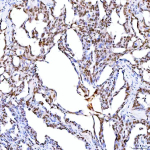

Immunohistochemical staining of SRRT using anti-SRRT antibody. SRRT was detected in a paraffin-embedded section of human lung adenocarcinoma tissue. Heat mediated antigen retrieval was performed in EDTA buffer (pH 8.0, epitope retrieval solution). The tissue section was blocked with 10% goat serum. The tissue section was then incubated with 2 ug/ml rabbit anti-SRRT antibody overnight at 4oC. Peroxidase Conjugated Goat Anti-rabbit IgG was used as secondary antibody and incubated for 30 minutes at 37oC. The tissue section was developed using an HRP secondary and DAB substrate.